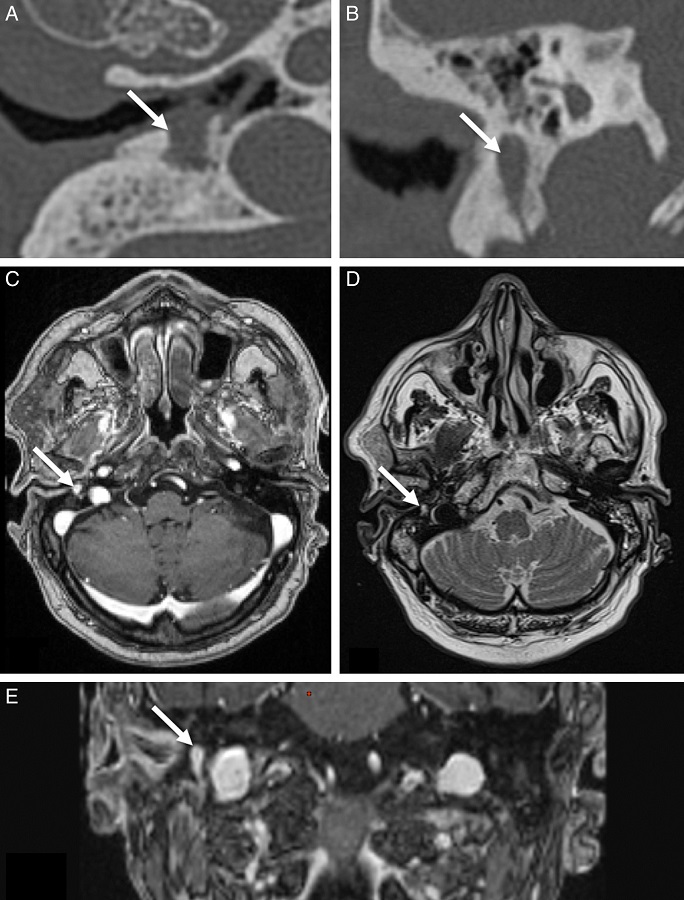

An 89-year-old male patient, who had had hypertension and type 2 diabetes mellitus for an extended period, presented to this tertiary care center with a six-month history of right earache, otorrhoea, and hearing loss. He had received oral antibiotics (amoxicillin-clavulanate) and local antibiotic eardrops during this interval. He denied tinnitus and vertigo. Otoscopic examination of the right ear revealed otorrhoea and inflammation of the EAC. The tympanic membrane was thickened and somewhat hemorrhagic in appearance but was otherwise intact. Cranial nerve examination revealed normal facial function. The patient reported no complaint of taste disturbance. Pure tone audiogram showed a right mixed hearing loss with air bone gap at 15 dB and symmetric bone curve by presbycusis. Laboratory signs of inflammation or infection were absent (no elevation of blood cell count, C-reactive protein [CRP], or erythrocyte sedimentation rate). Diabetes was considered to be well controlled (HbA1c = 5.6%). Cultures of otorrhoea were positive for Pseudomonas aeruginosa. P. aeruginosa was sensitive to ciprofloxacin and ceftazidime, and these systemic antibiotics were prescribed. Computed tomography (CT) and magnetic resonance imaging (MRI) of the temporal bone were performed. CT showed partial opacification of the right mastoid air cells and middle ear cavity, and thickening of the right tympanic membrane and skin of the right EAC. CT also revealed an osteolytic lesion of the mastoid along the vertical segment of the facial nerve, involving the floor of EAC, with bone destruction, decreased bone density, and the lake of continuity and wormy appearance of the cortical bone (Fig. 1). On MRI, multiple soft tissue signals were observed in the middle ear and mastoid region, displaying equal T1 and long T2 signals, with gadolinium contrast enhancement. MRI revealed EAC inflammation and infiltration of retrocondylar fat. Although, a soft tissue lesion of 6 mm equal T1 and long T2 signals with a homogenous hyper-enhancement after intravenous contrast injection, involved the floor of EAC, and caused an osteolytic erosion of the mastoid along the vertical segment of the facial nerve (Fig. 1). Under general anesthesia, with facial nerve neuromonitoring, the mass was accessed by the transmastoid approach to exclude a malignant tumor. A malignant tumor was first suspected, and the surgery aim was diagnostic before the therapeutic decision. Only a biopsy was performed, and the nerve was preserved during surgery. The biopsy revealed a tumor arising from the Schwann's cells (Fig. 2). Histological examination revealed a lesion composed of spindle cells with wavy appearing nuclei. The nuclei were arranged in a palisading fashion. Mitotic activity was not present. Moreover, in this particular case, inflammatory cells were associated. Spindle cells were diffusely and strongly positive for S100 protein. The postoperative period was uneventful, with well-preserved facial nerve function and no taste disturbance. Systemic antibiotics (ciprofloxacin and ceftazidime) were prescribed during six weeks for malignant external otitis, and periodic follow-ups were recommended for chorda tympani schwannoma. No attempt was made to resect the represented chorda tympani tumor because the patient was symptom-free. Follow-up at six months showed the patient in good health, without recurrent disease. Pure tone audiogram showed a stable bilateral sensorineural hearing loss.

To the best of the authors' knowledge, this is the first case in literature with incidental radiological finding of asymptomatic chorda tympani schwannoma. In this case, MOE may have caused right earache and mixed hearing loss. The schwannoma might be asymptomatic because the lesion was small. Otoscopic examination showed clinical presentation of MOE and lesion was not apparent. All of the previous cases showed a mass in the EAC or behind an intact tympanic membrane. Thus, this case is the first case in literature of asymptomatic chorda tympani schwannoma with no tumorous lesion at otoscopic examination. Babin described one post mortem study of asymptomatic chorda tympani, but otoscopic and imaging examination was not reported.3 Schwannomas are easily diagnosed by imaging, which, generally speaking, is very good at delineating the extension of the lesion and orienting the surgical procedures. However, in this study, the lesion measured 6 mm and MRI analysis was more difficult for the small lesion.

An osteolytic lesion along the chorda tympani must evoke a schwannoma. Although rare, this diagnosis should be considered in the same manner as a malignant tumor.